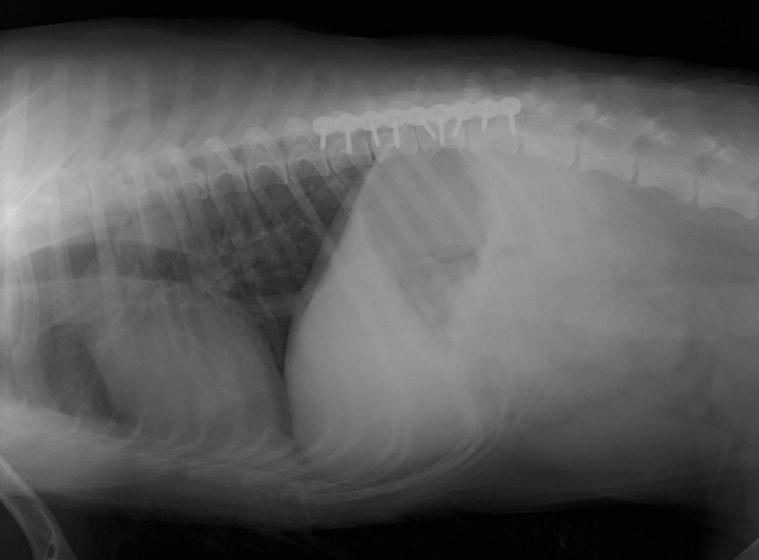

症例:交通事故による椎体脱臼

柴犬:9歳、避妊雌

交通事故直後、胸腰部に激しい疼痛、両後肢に完全麻痺を認め、シェフシェリントン徴候を呈していました。レントゲン検査において、第11-12胸椎間の脱臼が認められました。

脊髄の減圧、脊柱管の再構築・安定化を目的に、片側椎弓切除術およびMatrixMANDIBLE Plateによる椎体固定を実施しました。

隣接椎体を架橋するようにプレートを設置しました。

術後レントゲン写真